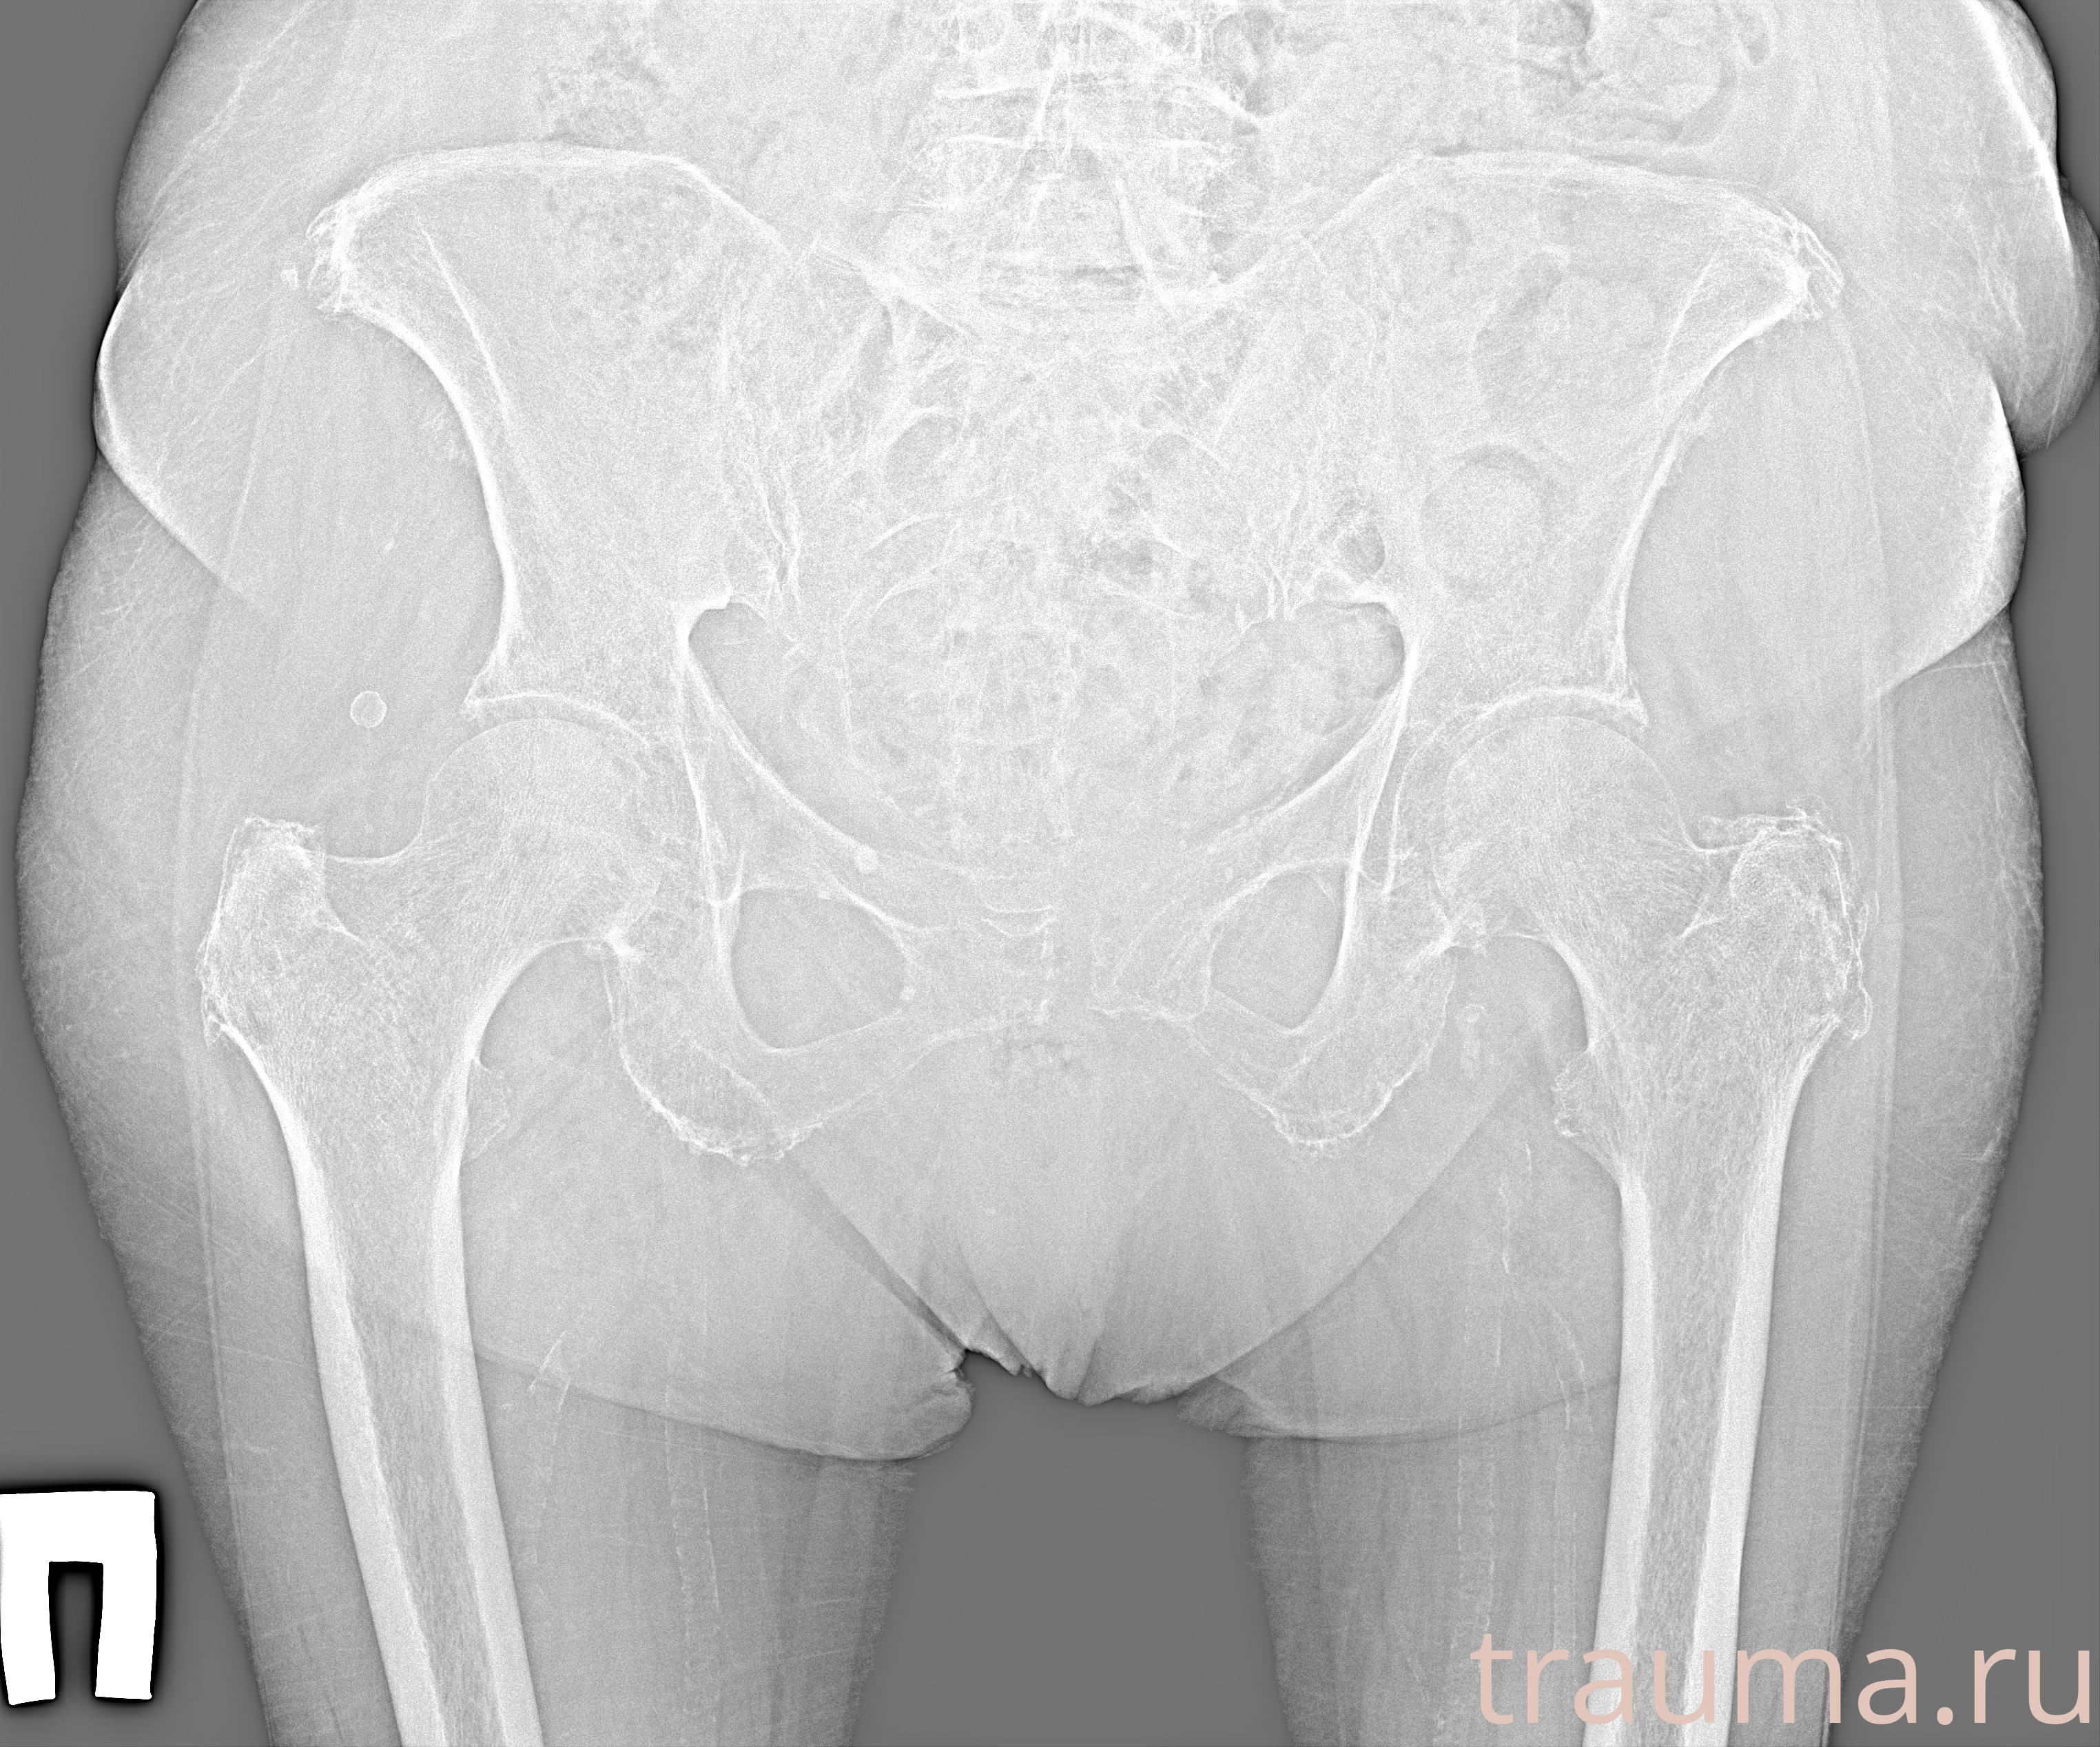

Рентгенограммы